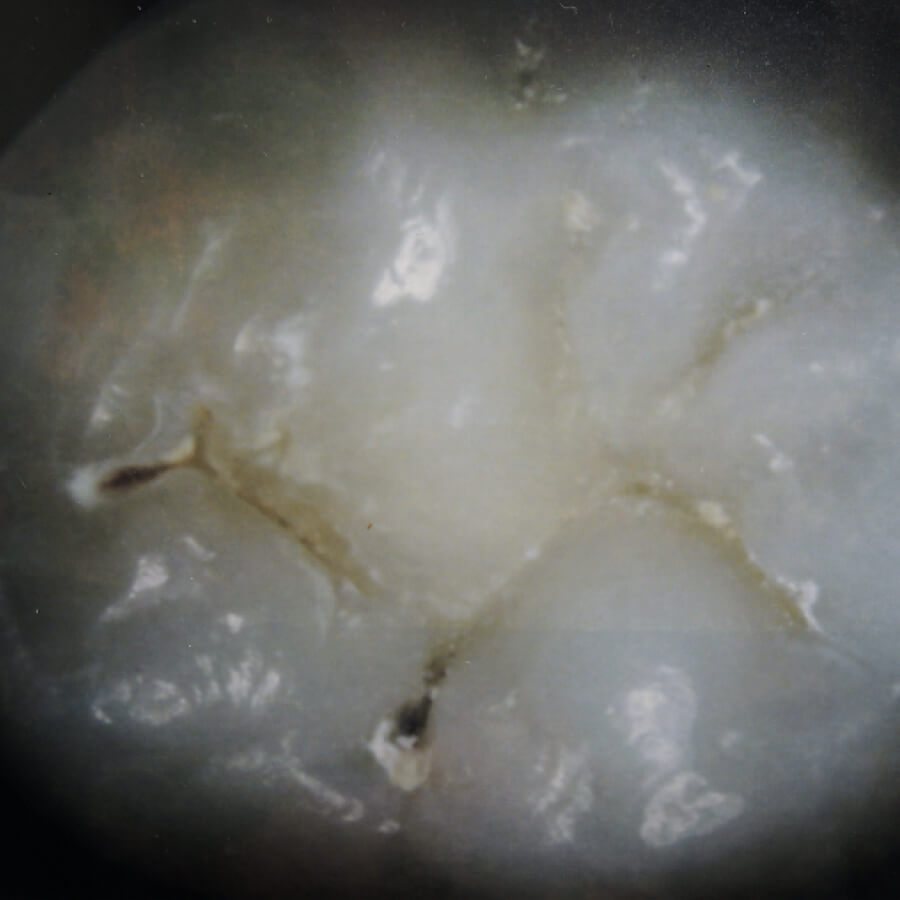

この画像は左は未処理のもの、右は人工エナメル質処理を施した天然歯を撮影したものです。

未処理

小臼歯

大臼歯

人工エナメル質処理

回人工エナメル質処理を行なった歯の画像